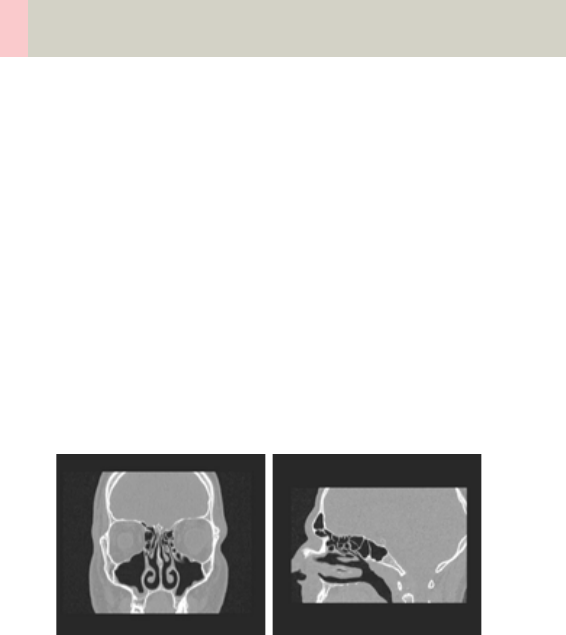

- SinusOrbit

Matrix 77

•Workflow 79

- Patient Position 79

- Auto Reference Lines 79

- Navigation within the Topogram 80